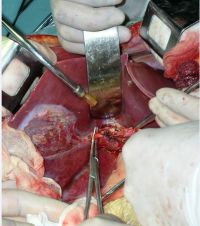

肝海绵状血管瘤手术切除

(1)充分显露肿瘤,一般作肋缘下斜切口,如果肿瘤位于右半肝,切口可自剑突沿右肋缘下至右第12肋;如果肿瘤位于左半肝,显露困难,则可以采用双肋缘下“人”字形切口,这样可充分显露肿瘤便于操作;对于需行右三叶切除的巨大肝血管瘤,必要时可作胸腹联合切口

(2)充分游离肝脏,在分离肿瘤和切肝前,可先结扎患侧肝动脉,使肿瘤缩小、变软,有利于手术操作。通常采用先在肝十二指肠韧带处放置一根橡皮管,以阻断入肝血流,更便于分离和切除肿瘤,且可防止手术过程中大出血。切肝前应仔细分离、切断和结扎肿瘤周围诸韧带及粘连组织,使肿瘤和患侧肝脏充分游离,游离的程度以达到术者可以用手握住肝切线并控制肝创面出血为原则。对于右肝巨大血管瘤已达肝后下腔静脉前壁者,充分游离右侧肝脏后,可以将肝脏向左侧翻转,仔细分离,暴露下腔静脉前壁的肝短静脉,逐根结扎,以免切肝时撕破下腔静脉壁或拉断肝短静脉。